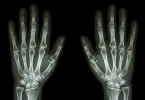

• 手指突然疼痛是什么原因

手指突然疼痛可能与外伤、关节炎、腱鞘炎、痛风、雷诺综合征等因素有关。手指突然疼痛通常表现为局部红肿、活动受限、刺痛或钝痛等症状,建议及时就医明确诊断。1、外伤手指受到撞击、挤压或切割等外力作用可能导致 ...

• 手指关节疼痛肿胀挂什么科

手指关节疼痛肿胀挂什么科

手指关节疼痛肿胀可挂风湿免疫科、骨科或内分泌科,可能与骨关节炎、类风湿关节炎、痛风性关节炎等因素有关。一、风湿免疫科若伴随晨僵、对称性肿痛或关节变形,需优先排查类风湿关节炎。该病与自身免疫异常相关,典 ...